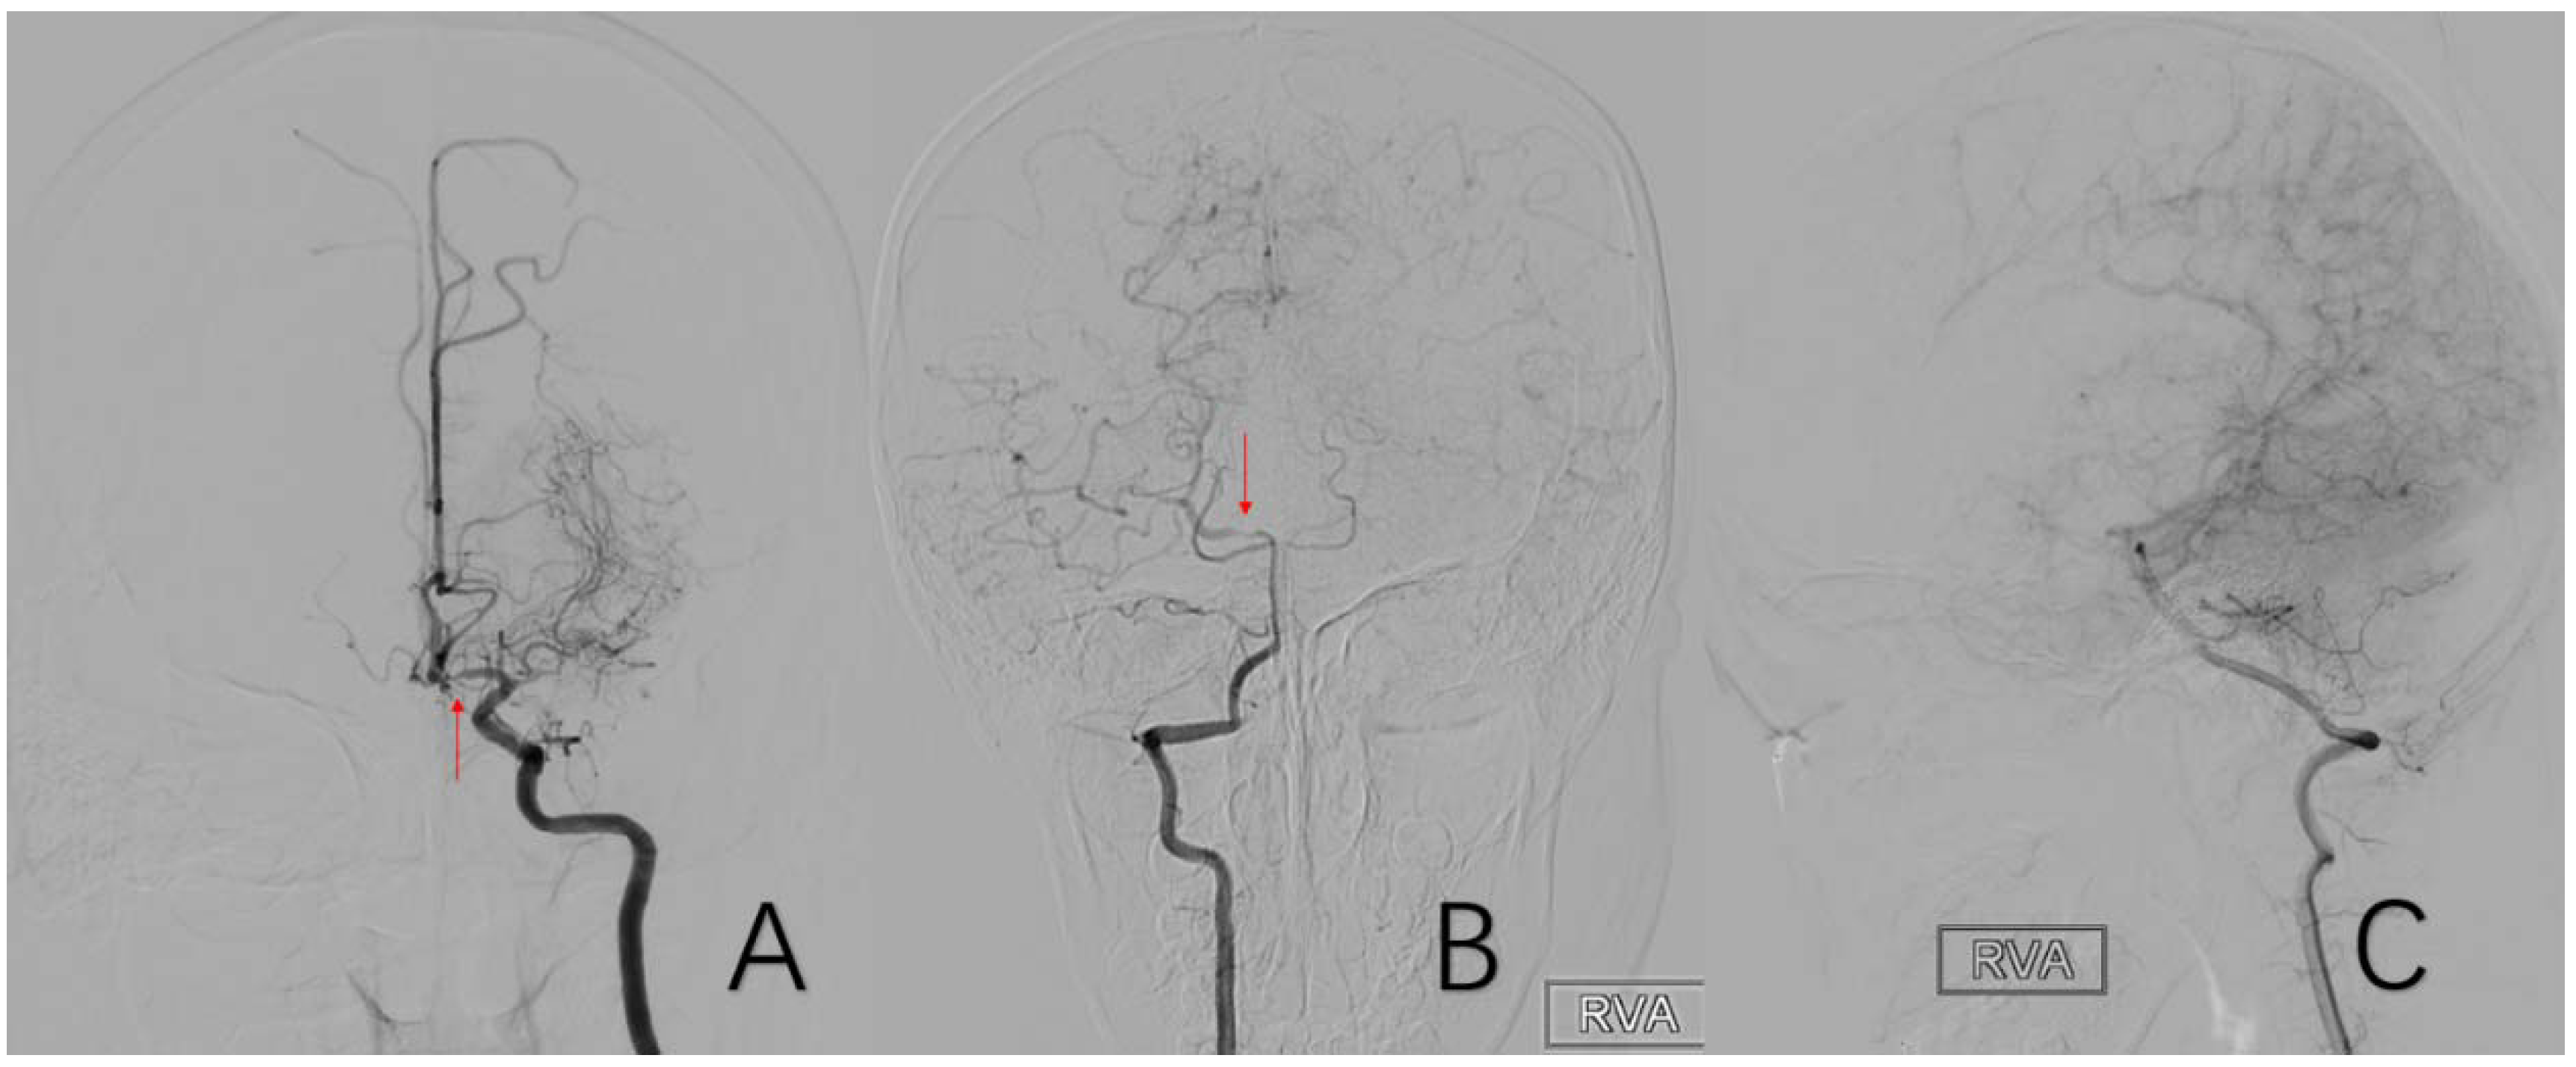

2.3.11. Factor 6 Unstable Compensation

2.3.12. Factor 7 Extracranial Arterial Compensation